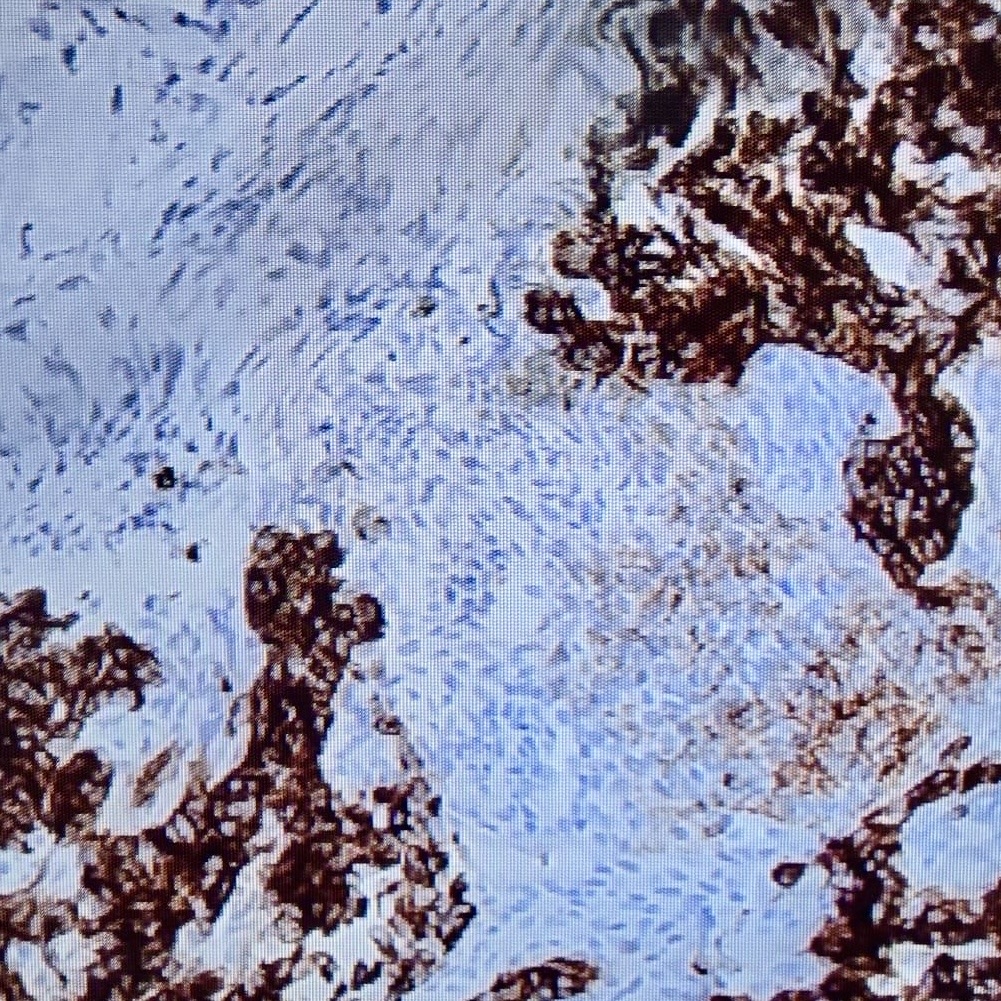

Patient underwent a TTE guided endomyocardial biopsy which confirmed diagnosis of biphasic synovial sarcoma with SS18 rearrangement. The patient was started on doxorubicin and ifosfamide. However, he had adverse reaction from ifosfamide. PET scan did not show any evidence of local or distant metabolically active metastasis. At this point patient’s liver function test has improved. After multidisciplinary discussion patient was planned to continue doxorubicin therapy as an outpatient pending final surgical decision after recovery from acute rehabilitation. RV mass reduced in size on subsequent TTE. Patient is currently under evaluation of surgical resection or advance therapy.